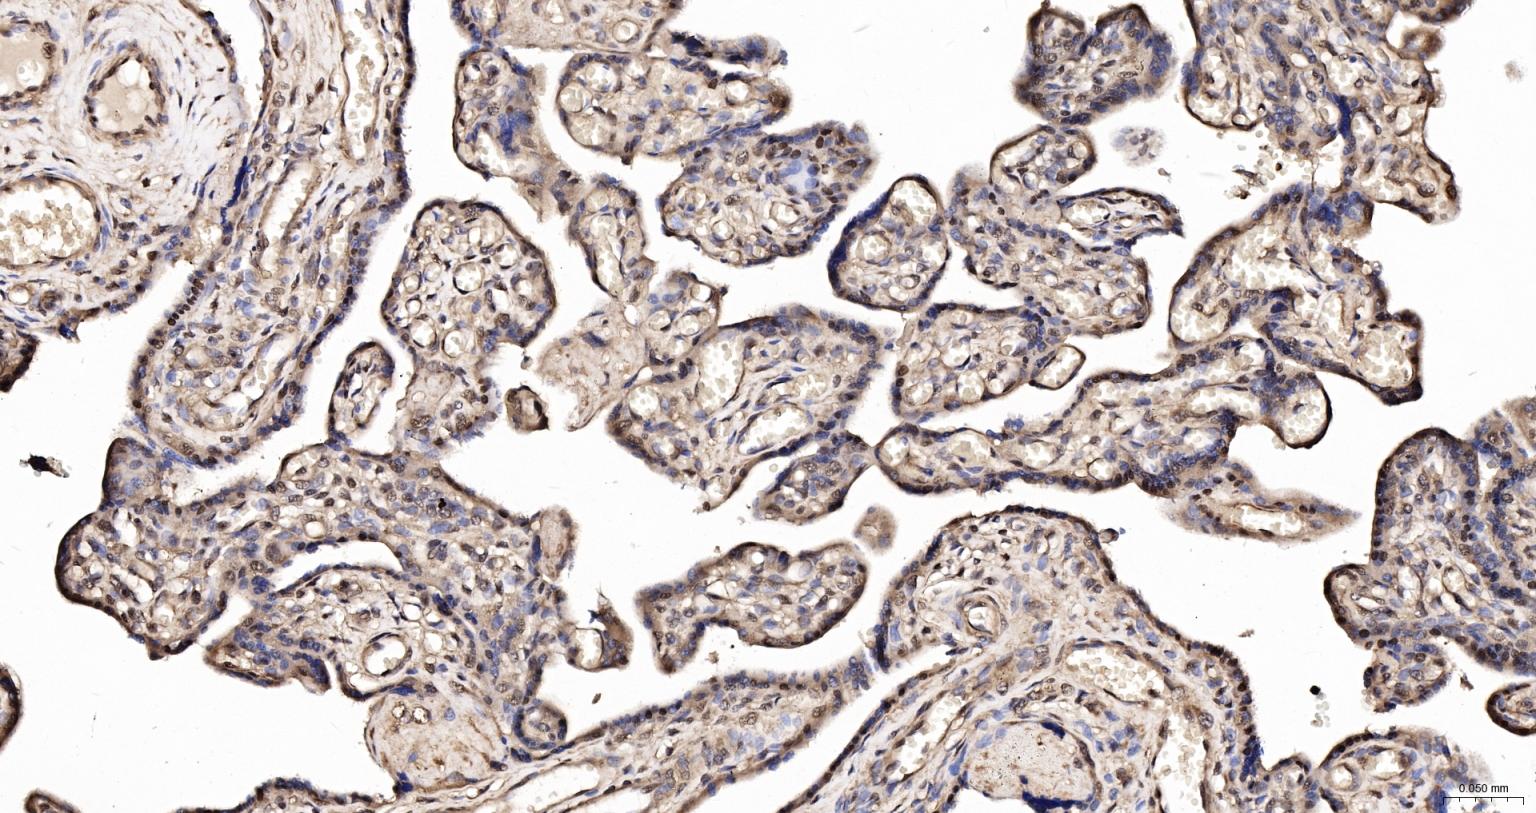

Paraformaldehyde-fixed, paraffin embedded Human Placenta; Antigen retrieval by boiling in sodium citrate buffer (pH6.0) for 15 min; The section was incubated with HDGF Monoclonal Antibody, Unconjugated (bsm-62928R) at 1:200 overnight at 4°C, followed by conjugation to the bs-0295G-HRP and DAB (C-0010) staining.